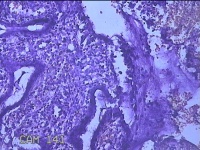

宫颈3点、9点、11点、12点组织

性别

女

年龄

37岁

临床诊断

人乳头瘤病毒感染

一般病史

HPV其他12型阳性

标本名称

大体所见

1.“宫颈3点组织”:灰白粉红色组织1x0.8x0.2cm一块。 2.“宫颈9点组织”:灰白粉红色组织0.7x0.5x0.2cm一块。 3.“宫颈11点组织”:灰白粉红色组织0.8x0.5x0.2cm一块。 4.“宫颈12点组织”:灰白粉红色组织8.5x0.5x0.2cm一块。

图3